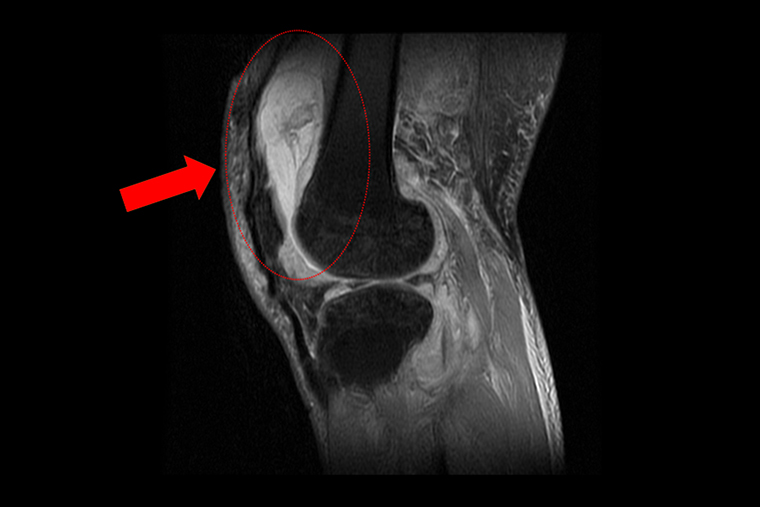

收治這名個案的台中慈濟醫院關節中心主任周立展表示,賴先生在就診時自認只是罹患退化性關節炎,但過去數月在服用止痛藥、抽取關節積水、熱敷復健後卻不見改善,症狀反而越來越嚴重,來院時膝蓋已明顯腫脹且無法彎曲。隨即安排抽取關節液化驗,發現其白血球數值雖偏高,但並非典型的細菌感染,懷疑有其他原因。於是便進一步安排個案住院,接受X光與磁振造影檢查,結果顯示其膝蓋內已有大量積液並化膿,屬於嚴重關節感染。

▲個案的磁振造影顯示膝蓋內已有大量積液並出現化膿的情形。(圖/台中慈濟醫院提供)